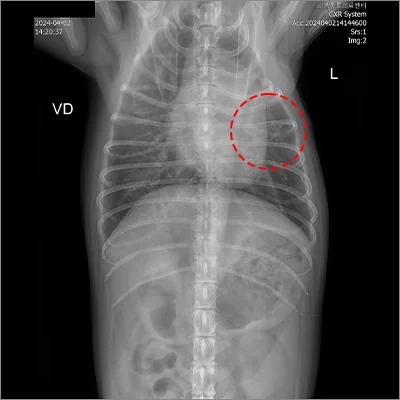

📍 폐엽절제

폐엽절제 전

폐엽절제 후

정확한 진단과 수술로 삶의 질을 회복합니다